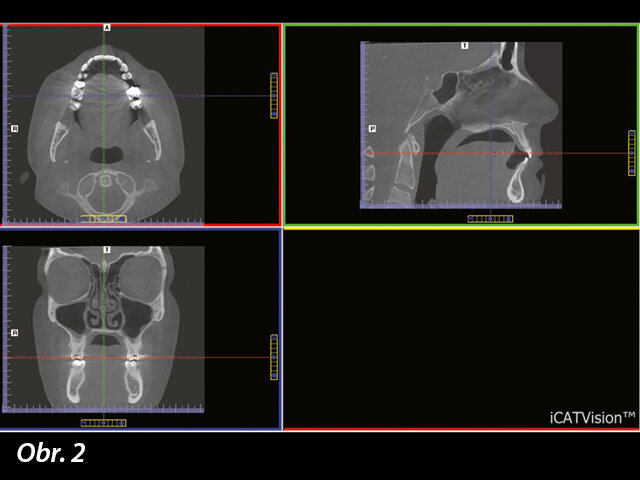

Jakmile je skenování dokončeno, 3D zobrazovací software umožní přesně replikovat polohu, tvary a měření skenovaných oblastí: horní a dolní čelisti, kloubů, nosní dutiny i vedlejších dutin nosních a dalších tkání až po krční páteř. Navíc tato zobrazovací metoda může vytvářet axiální, koronální a sagitální řezy, které dříve nebylo možno získat (obr. 2). V rámci softwaru lze tyto řezy přesně určit a rotovat v rámci diagnostiky a plánování léčby.